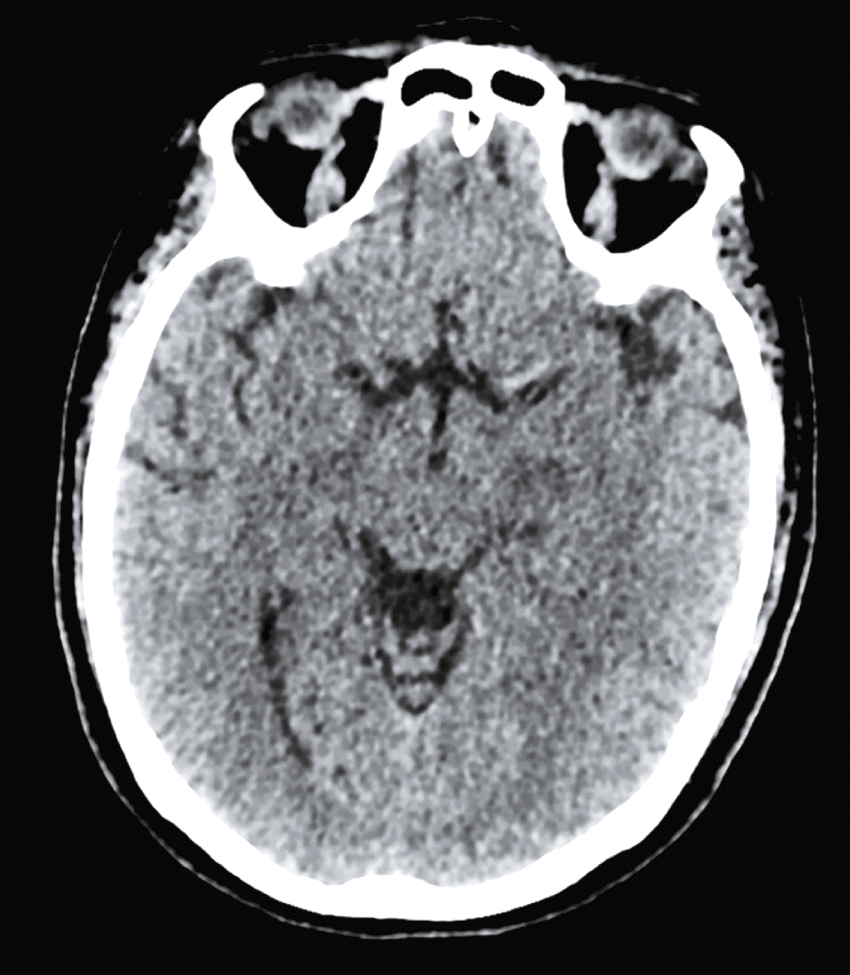

Question 4 – QRMVoici une coupe axiale d’un scanner cérébral sans injection (fig. 31.9). Concernant son interprétation, quelle(s) est (sont) la (les) proposition(s) exacte(s) ?

Fig. 31.9 L'image montre une coupe transversale d'un scanner cérébral (CT scan) d'un cerveau humain. Cette image en noir et blanc présente des détails anatomiques du cerveau, y compris les structures internes et les contours du crâne. Les zones claires représentent les tissus osseux, tandis que les zones sombres indiquent les tissus mous du cerveau. On peut observer des variations dans les nuances de gris qui révèlent différentes densités de tissus. Les ventricules cérébraux, qui sont des cavités remplies de liquide céphalo-rachidien, sont également visibles au centre de l'image. Ces cavités apparaissent sombres en contraste avec les tissus environnants. La partie périphérique de l'image montre les os du crâne, apparaissant comme des lignes blanches bien définies. Les scanners cérébraux sont des outils essentiels pour diagnostiquer et surveiller diverses conditions neurologiques. Ils permettent de détecter des anomalies telles que des hémorragies, des tumeurs ou des lésions cérébrales. Les variations de teintes visibles sur l'image aident à différencier les structures et à évaluer leur état, fournissant ainsi des informations cruciales pour les professionnels de la santé. Grâce à ces images détaillées, il est possible de planifier des traitements adaptés et de surveiller l'évolution des pathologies cérébrales.

- A hyperdensité spontanée des vallées sylviennes

- B hyperdensité spontanée du sinus maxillaire droit

- C hypodensité spontanée de l’épiphyse

- D hyperdensité spontanée du 4e ventricule

-

E hypodensité spontanée des plexus choroïdes